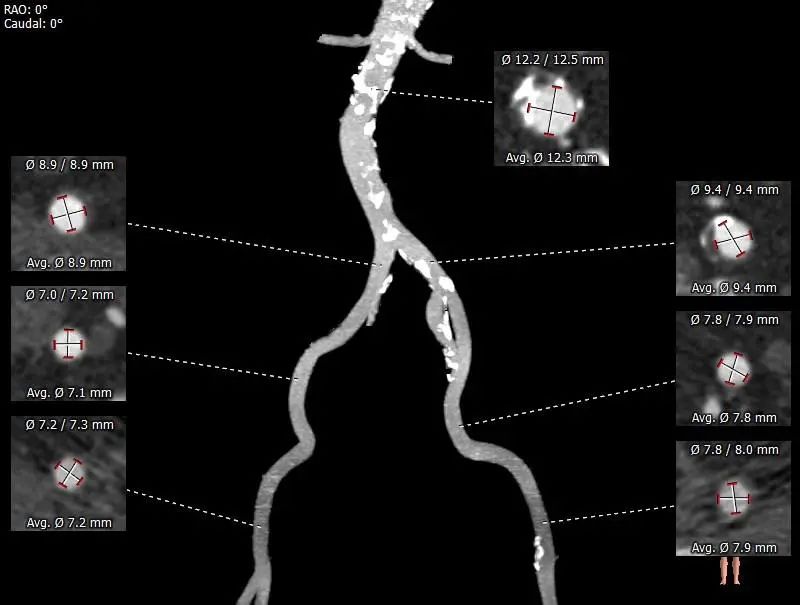

外周入路走行适宜,腹主中下端及左髂总动脉散在钙化,血管内壁不规则增厚。

外周血管及主动脉弓解剖